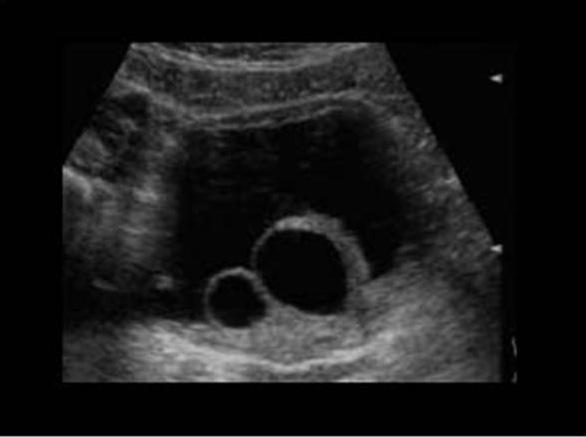

rectal bleeding

Intussception

vomiting

abdominal pain

rectal bleeding

Intussception